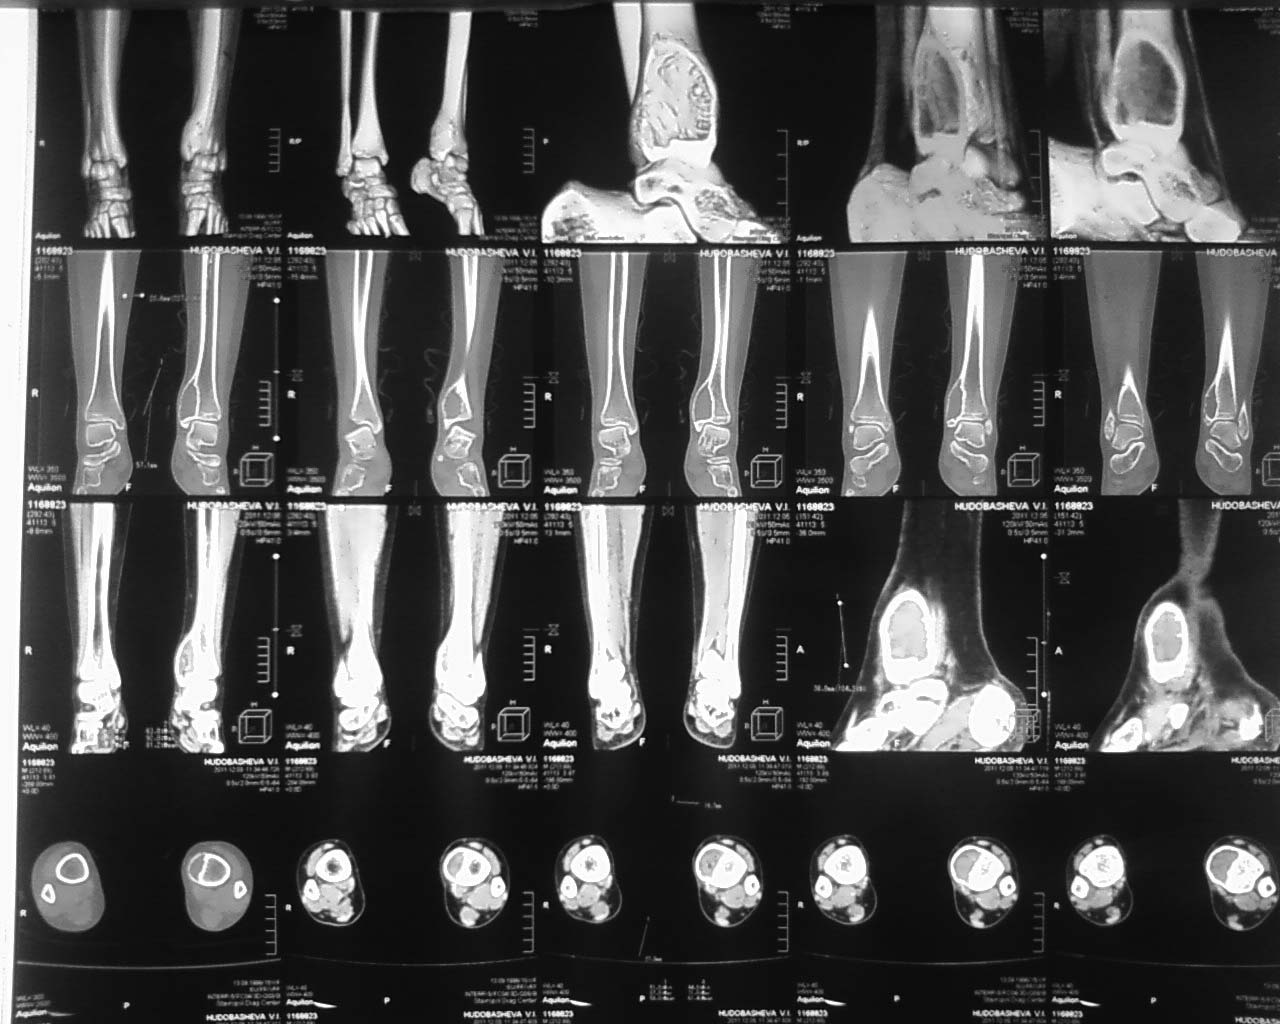

Здравствуйте уважаемые коллегиПомоги определится с тактикой лечения больного ребенка 15 лет. Жалобы на наличие опухолевидного образования в нижней трети левой голени. Болеет с апреля 2011 г., обратились к врачу по м/ж в ноябре 2011, после проведения рентгенографии и КТ направлена к нам с диагнозом: остеобластокластома дистального метафиза левой б/берцовой кости.Локально: определяется умеренная болезненность при пальпации н/3 голени. Планируется выполнить биопсию.

Уважаемые коллеги, спасибо за участие в обсуждении нашего случая. Мы прооперировали больную - выполнили внутреннюю резекцию очага опухоли, костная пластика трансплантатом из малоберцовой кости. Вашему вниманию предоставляем снимок.